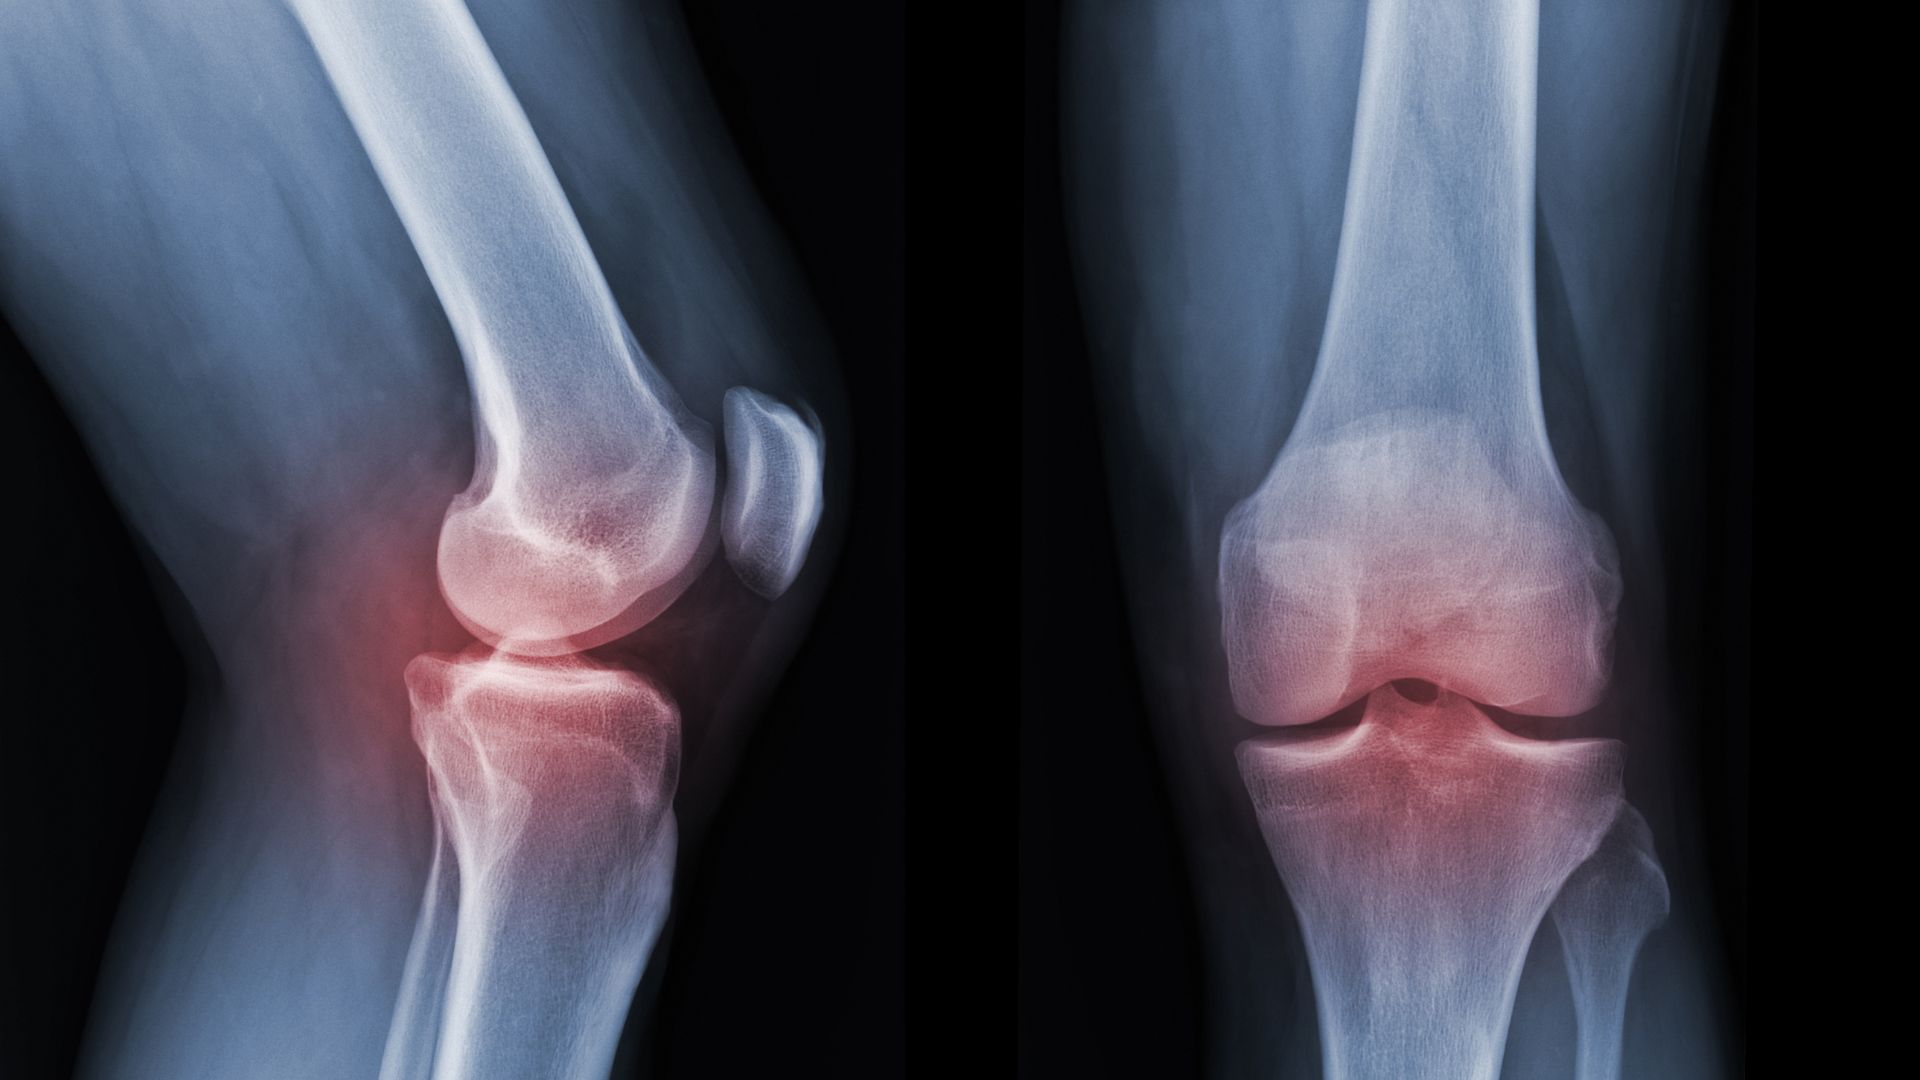

A gota é uma forma de artrite causada pelo acúmulo de cristais de ácido úrico nas articulações, o que provoca crises de dor intensa, vermelhidão e inchaço — geralmente começando no dedão do pé. A doença pode se tornar crônica se não for tratada. Com o uso de medicamentos e mudanças no estilo de vida, é possível controlar bem as crises e prevenir novas.

É uma forma de artrite inflamatória que afeta principalmente a coluna vertebral, causando dor lombar e rigidez, especialmente ao acordar. Com o tempo, pode haver fusão entre as vértebras. O tratamento visa aliviar os sintomas e preservar a mobilidade da coluna.

Essas condições são comuns e afetam músculos, tendões, articulações e ossos.

O tratamento varia de acordo com a causa e pode envolver medicamentos, fisioterapia e mudanças no estilo de vida.